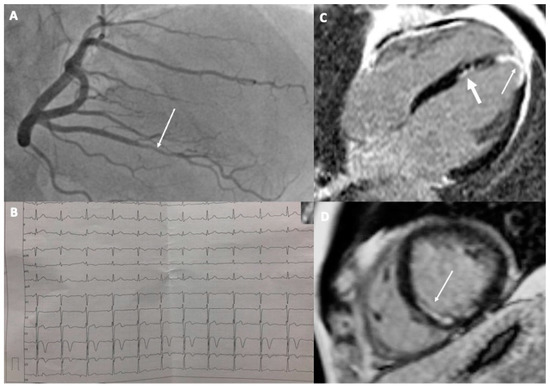

A 37-year-old male amateur athlete was admitted to the hospital due to severe chest and back pain. He had performed strenuous swimming training a day before the presentation. His ECG was unremarkable but biochemical examination revealed a markedly elevated concentration of troponin I, atypical for the exercise (>5 times the upper reference limit). For this reason, he was referred for a coronary angiogram but no changes were found. The pain subsided after a few hours. An MI with non-obstructed coronary arteries (MINOCA) was diagnosed and the patient was sent for cardiac magnetic resonance (CMR), which showed the presence of edema and small subendocardial late gadolinium enhancement (LGE) in the interventricular septum, typical for recent myocardial infarction in the area of the right coronary artery (RCA) supply. A thorough examination of the coronary angiogram demonstrated a lower opacification of one of the branches of RCA (Figure 1A). The patient was given a small dose of aspirin, high-dose of statin, and angiotensin convertase inhibitor (ACE-I). He had no hyperlipidemia, normal blood pressure, normal body weight, followed a healthy diet, and was not a smoker. He also did not have any family history of myocardial infarctions. However, he admitted to living under a great amount of psychological stress. After a few months, he resigned from medications and returned to physical activity. A year later he was admitted to the hospital again with similar symptoms, only this time after running. There were visible ischemic changes in the ECG in the form of a T-wave inversion in leads V4–V5 (Figure 1B) but again no changes in the coronary angiogram. The second CMR disclosed the normal size of the heart chambers, with preserved global left ventricular systolic function (LVEF = 57%) but with apical akinesia and hypokinesia of the apical segment of the septum and partly of the middle infero-septal segment of the left ventricle. Therefore apart from the prior MI, there were also features of the new, healing transmural left ventricular apical infarction (Figure 1C,D). This time, the patient was instructed to remain on aspirin, statin, and a small dose of ACE-I and to avoid strenuous exercises. His LDL cholesterol concentration remained below 55 mg%. It is hard to unanimously establish the cause of MI in the presented case; however, based on the available examinations, it was caused most likely by the erosion of a small, but unstable, atherosclerotic plaque. The incidents could have been provoked by the sudden rise in blood pressure with or without coronary artery spasm during a bout of intensive exercise. As intravascular imaging was not performed and would be probably impossible given the small diameter of the affected arteries, a final etiology could not be found. The patient refused to undergo computed tomography of the coronary arteries (CTCA) to analyze the presence of coronary calcifications and plaques. The patient has remained free of sequels for 2 years from the second event.

Figure 1.

A 37-year-old athlete with recurrent MI: (A) Coronary angiogram of the right coronary artery with visible lower opacification in one of the branches (arrow); (B) Electrocardiogram with visible signs of ischemia in the form of T-wave inversion in V4 and V5; (C,D) Cardiac magnetic resonance images after second MI showing subendocardial scar in the interventricular septum and in the apex typical for myocardial infarction (thin arrows). Previous MI is visible in the interventricular septum ((C)—thicker arrow).